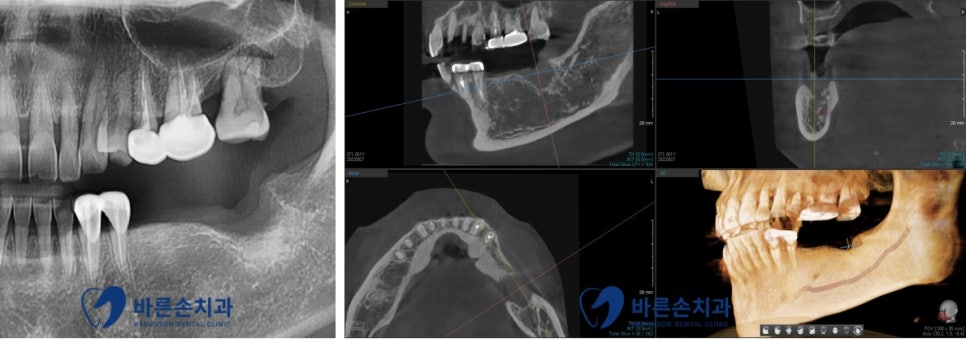

임플란트 진행 전

정확한 진단을 위해 파노라마 및 3D-CT 촬영을 한 후

치조골 상태 및 임플란트의 식립 위치 등을 확인합니다